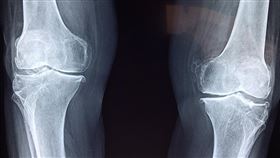

輕微碰撞就骨折 竟是癌症「骨轉移」

惡性腫瘤生長過程中,癌細胞容易藉由血液、淋巴,轉移到...

2020/11/16 11:00